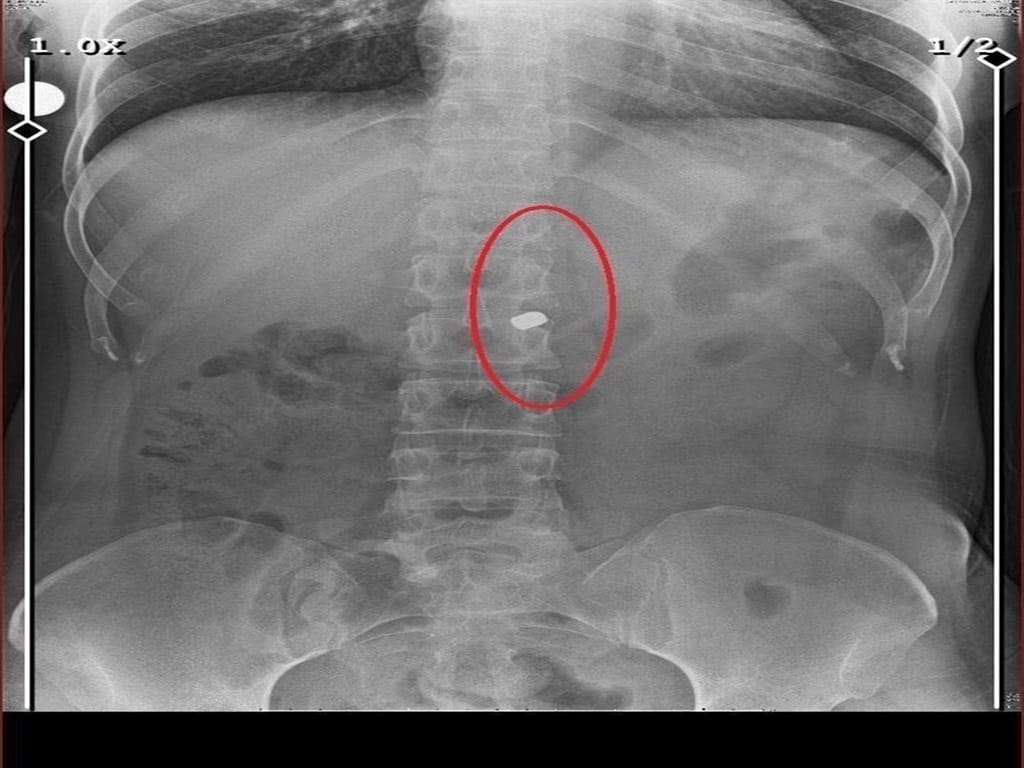

Saldırgan, aynı silahla sevgilisi Fatma O.’yu da 8 kurşunla yaraladı. Olayın ardından evin içinde tam bir kabus yaşandı. Arkadaşının cesedini önce çarşafa, ardından kokmasın diye streç filme sarıp bantlayan Sarıkaya, yaralı sevgilisini hastaneye götürmek yerine eczaneden aldığı malzemelerle evde tedavi etmeye çalıştı. Fatma O., yaralı haldeyken 21 gün boyunca evde rehin tutuldu ve bu süre zarfında defalarca cinsel saldırıya uğradı.